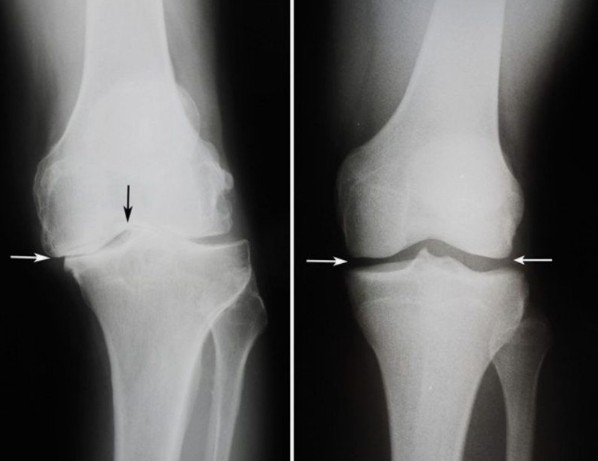

След курса с Hondrodox ставите напълно се възстановиха